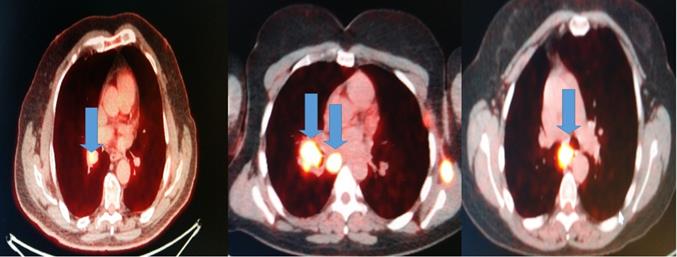

All patients had before the EBUS-TBNA PET-CT performed. We made four punctures to the most positive lymphnode according to each PET-CT and a cell block was created from each lymphnode Figure 2.

Figure 2

Blue arrows indicate the positive lymphnodes that were punctured (SUV>3).